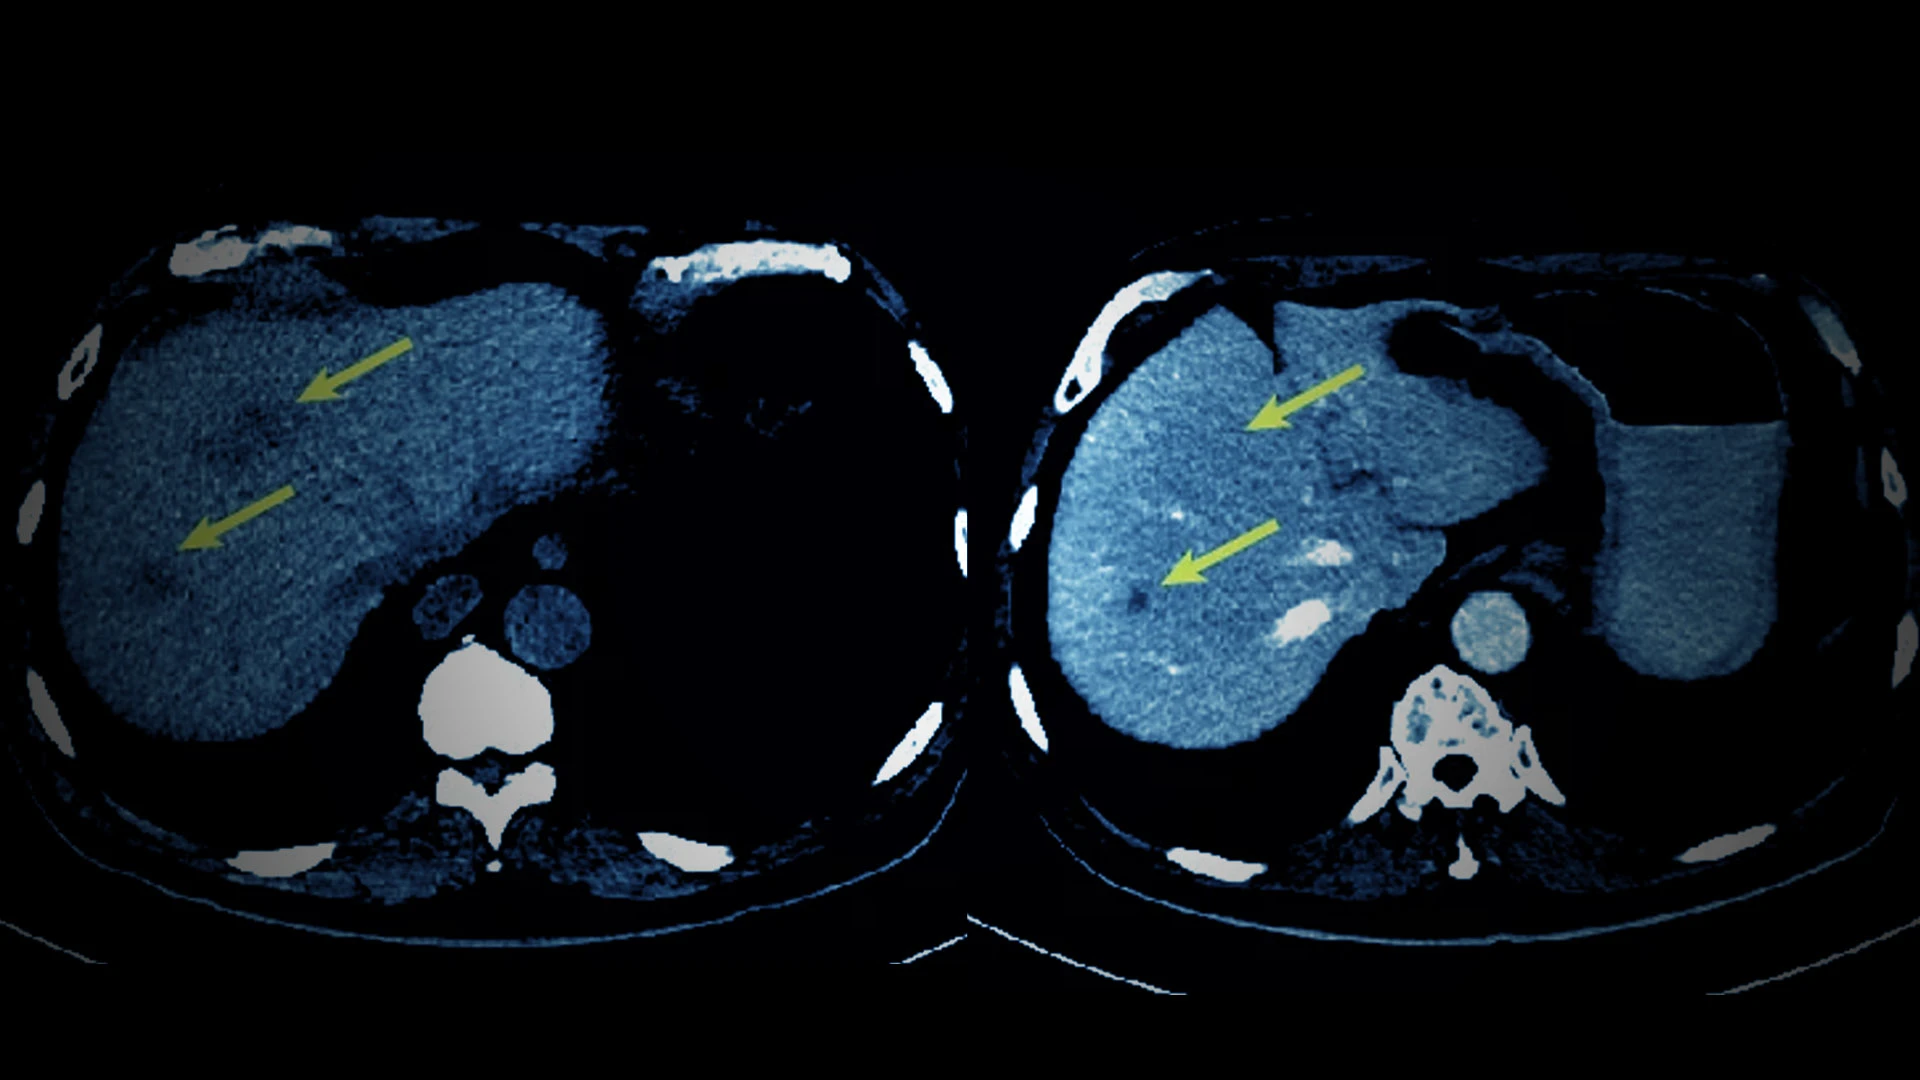

PGV001 neoantigens are predicted using the OpenVax platform, which involves a workflow that begins with identifying somatic variants from tumor/normal exome sequencing, seen above. For each identified mutation with a predicted coding effect—missense, frameshift, or stop loss—tumor RNA sequencing (RNA-seq) is used to confirm expression and correctly phase the somatic mutation with any nearby germline polymorphisms. The platform then generates several candidate vaccine peptides, which are analyzed for binding to a patient's HLA class I alleles.